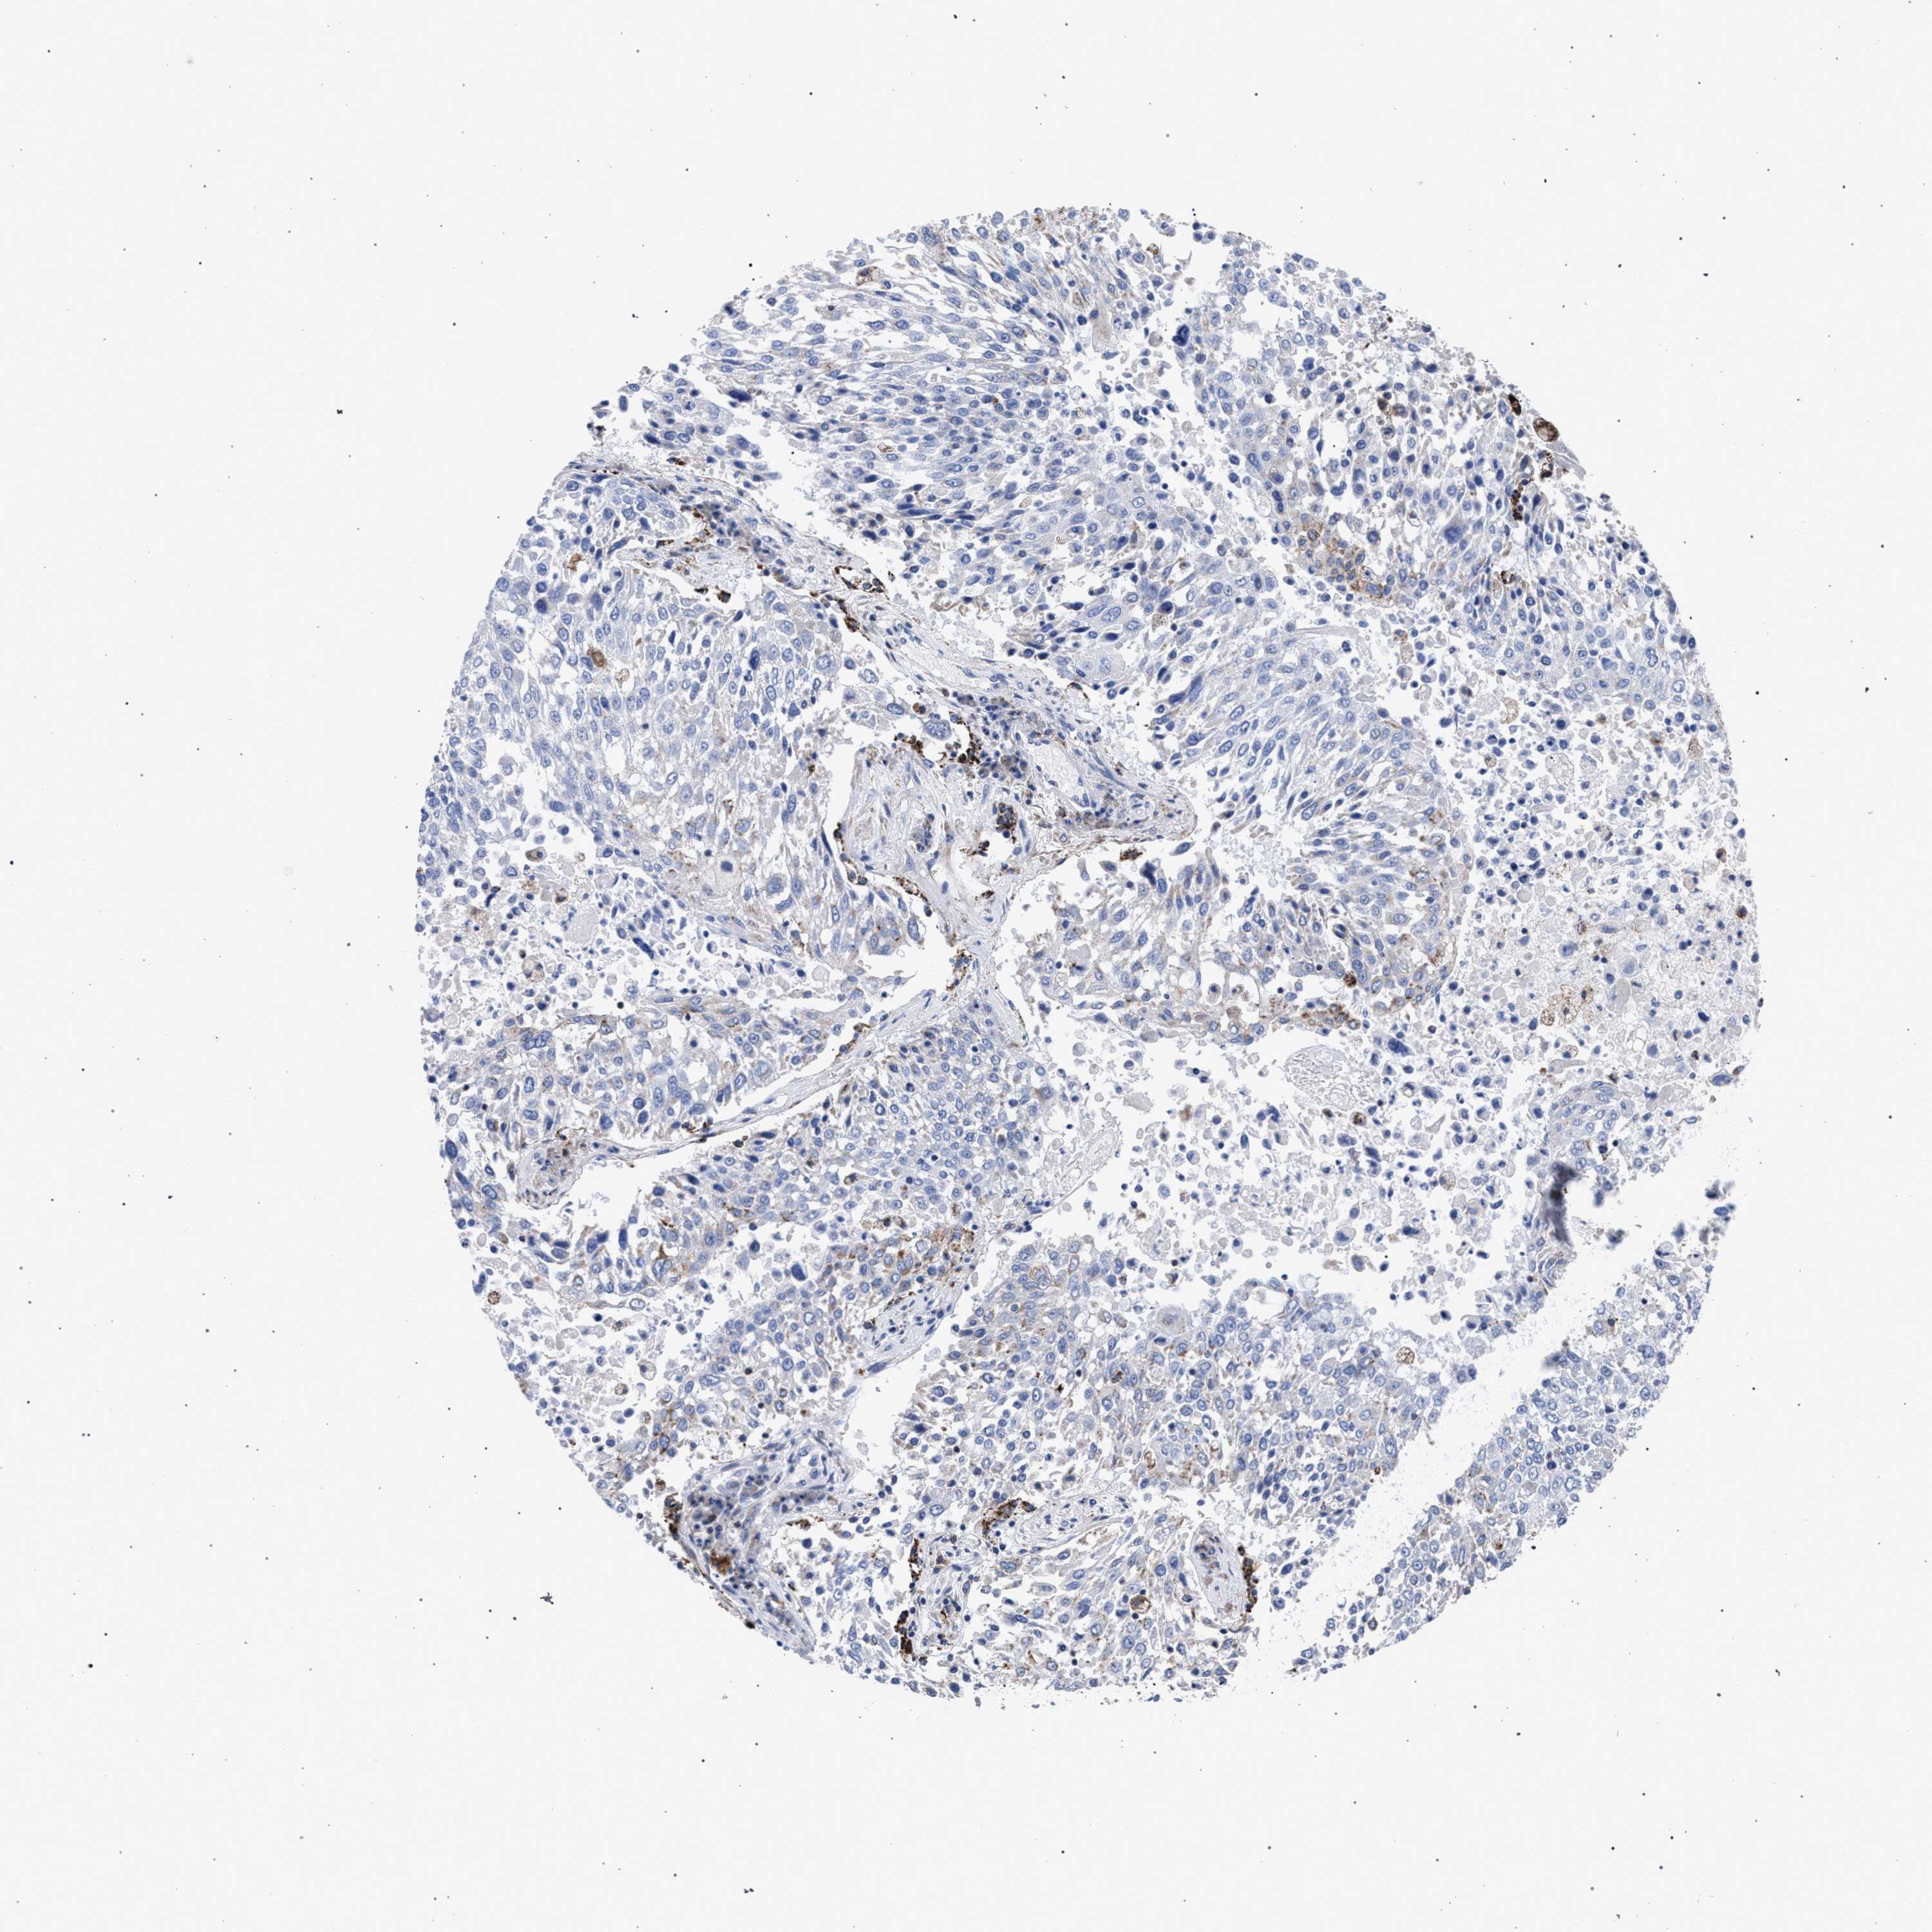

LUNG ADENOCARCINOMA (TCGA) - Interactive survival scatter ploti

The Survival Scatter plot shows the clinical status (i.e. dead or alive) for all individuals in the patient cohort, based on the same data that underlies the corresponding Kaplan-Meier plots. Patients that are alive at last time for follow-up are shown in blue and patients who have died during the study are shown in red.

The x-axis shows the expression levels (FPKM) of the investigated gene in the tumor tissue at the time of diagnosis. The y-axis shows the follow-up time after diagnosis (years). Both axes are complimented with kernel density curves demonstrating the data density over the axes. The top density plot shows the expression levels (FPKM) distribution among dead (red) and alive patients (blue). The right density plot shows the data density of the survived years of dead patients with high and low expression levels respectively, stratified using the cutoff indicated by the vertical dashed line through the Survival Scatter plot. This cutoff is automatically defined based on the FPKM cutoff that minimizes the p-score. The cutoff can be changed by dragging the vertical line or by entering a cutoff value in the square labeled "Current cut-off".

Under the Survival Scatter plot the p-score landscape (black curve; left axis) is shown together with dead median separation (red curve; right axis). Dead median separation is the difference in median mRNA expression between patients who have died with high and low expression, respectively. It is calculated as follows: median FPKM expression of dead patients with high expression - median FPKM expression of dead patients with low expression. This is intended to aid the user in visually exploring custom cutoffs and the associated p-scores and dead median separation.

Individual patient data is displayed and can be filtered by clicking on one or more of the category buttons on the top of the page. Categories describing expression level and patient information include: high, low, alive, dead, female, male and tumor stages. The scale of the x-axis can be toggled between linear and log-scale by clicking on the "x log" button. Mouse-over function shows TCGA ID, patient information and mRNA expression (FPKM) for each patient.

& Survival analysisi

Kaplan-Meier plots summarize results from analysis of correlation between mRNA expression level and patient survival. Patients were divided based on level of expression into one of the two groups "low" (under cut off) or "high" (over cut off). X-axis shows time for survival (years) and y-axis shows the probability of survival, where 1.0 corresponds to 100 percent.

ACADS is not prognostic in Lung Adenocarcinoma (TCGA)

: 14.54

Average pTPM 20.9

Number of samples 497